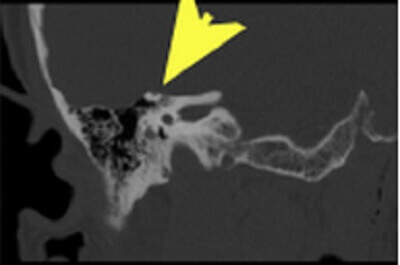

Diagnosis: Dehiscence of the right superior semicircular canal

Figure 1: Coronal reformats from a temporal bone CT (using a bone reconstruction algorithm with thin sections through the right internal auditory canal) demonstrate absence of bone (yellow arrow) covering the roof of the superior surface of the semicircular canal (red arrow). This finding is pathogmnemonic for dehiscence of the superior semicircular canal.

This is best appreciated on the reformatted images from an internal auditory canal protocol CT – coronal and semioblique, sagittal and coronal reformats will show the absence of the superior aspect of the otic capsule on more than one slice. The diagnosis can be challenging however because it is excluded by even a thin bony roof that can exist at or below the resolution of modern CT or be masked by partial volume averaging with adjacent slices